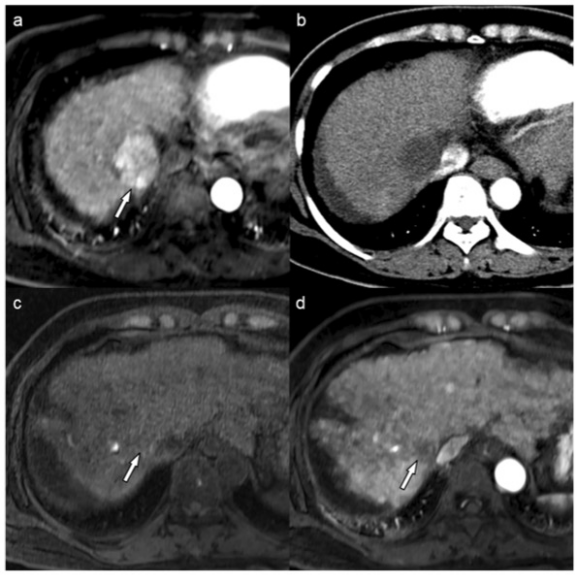

圖 50歲女性肝細(xì)胞癌(HCC)的MR和CT圖像。動(dòng)脈期MR圖像顯示肝臟第7段有一個(gè)4.2厘米的HCC(箭頭)(a)。經(jīng)過(guò)一個(gè)療程的藥物洗脫珠-TACE治療后,患者獲得了持久的影像學(xué)完全反應(yīng)(b)。肝移植時(shí),對(duì)比前(c)和動(dòng)脈期(d)的MR圖像將目標(biāo)病變分配為LR-TR非生存類(lèi)別(箭頭)。術(shù)前血清AFP水平為3.3納克/毫升。風(fēng)險(xiǎn)評(píng)分為0,患者屬于有利的風(fēng)險(xiǎn)組。手術(shù)后,證實(shí)了病理上可行的腫瘤,60%的腫瘤已經(jīng)壞死?;颊咴谛g(shù)后104.6個(gè)月內(nèi)一直存活且無(wú)復(fù)發(fā)